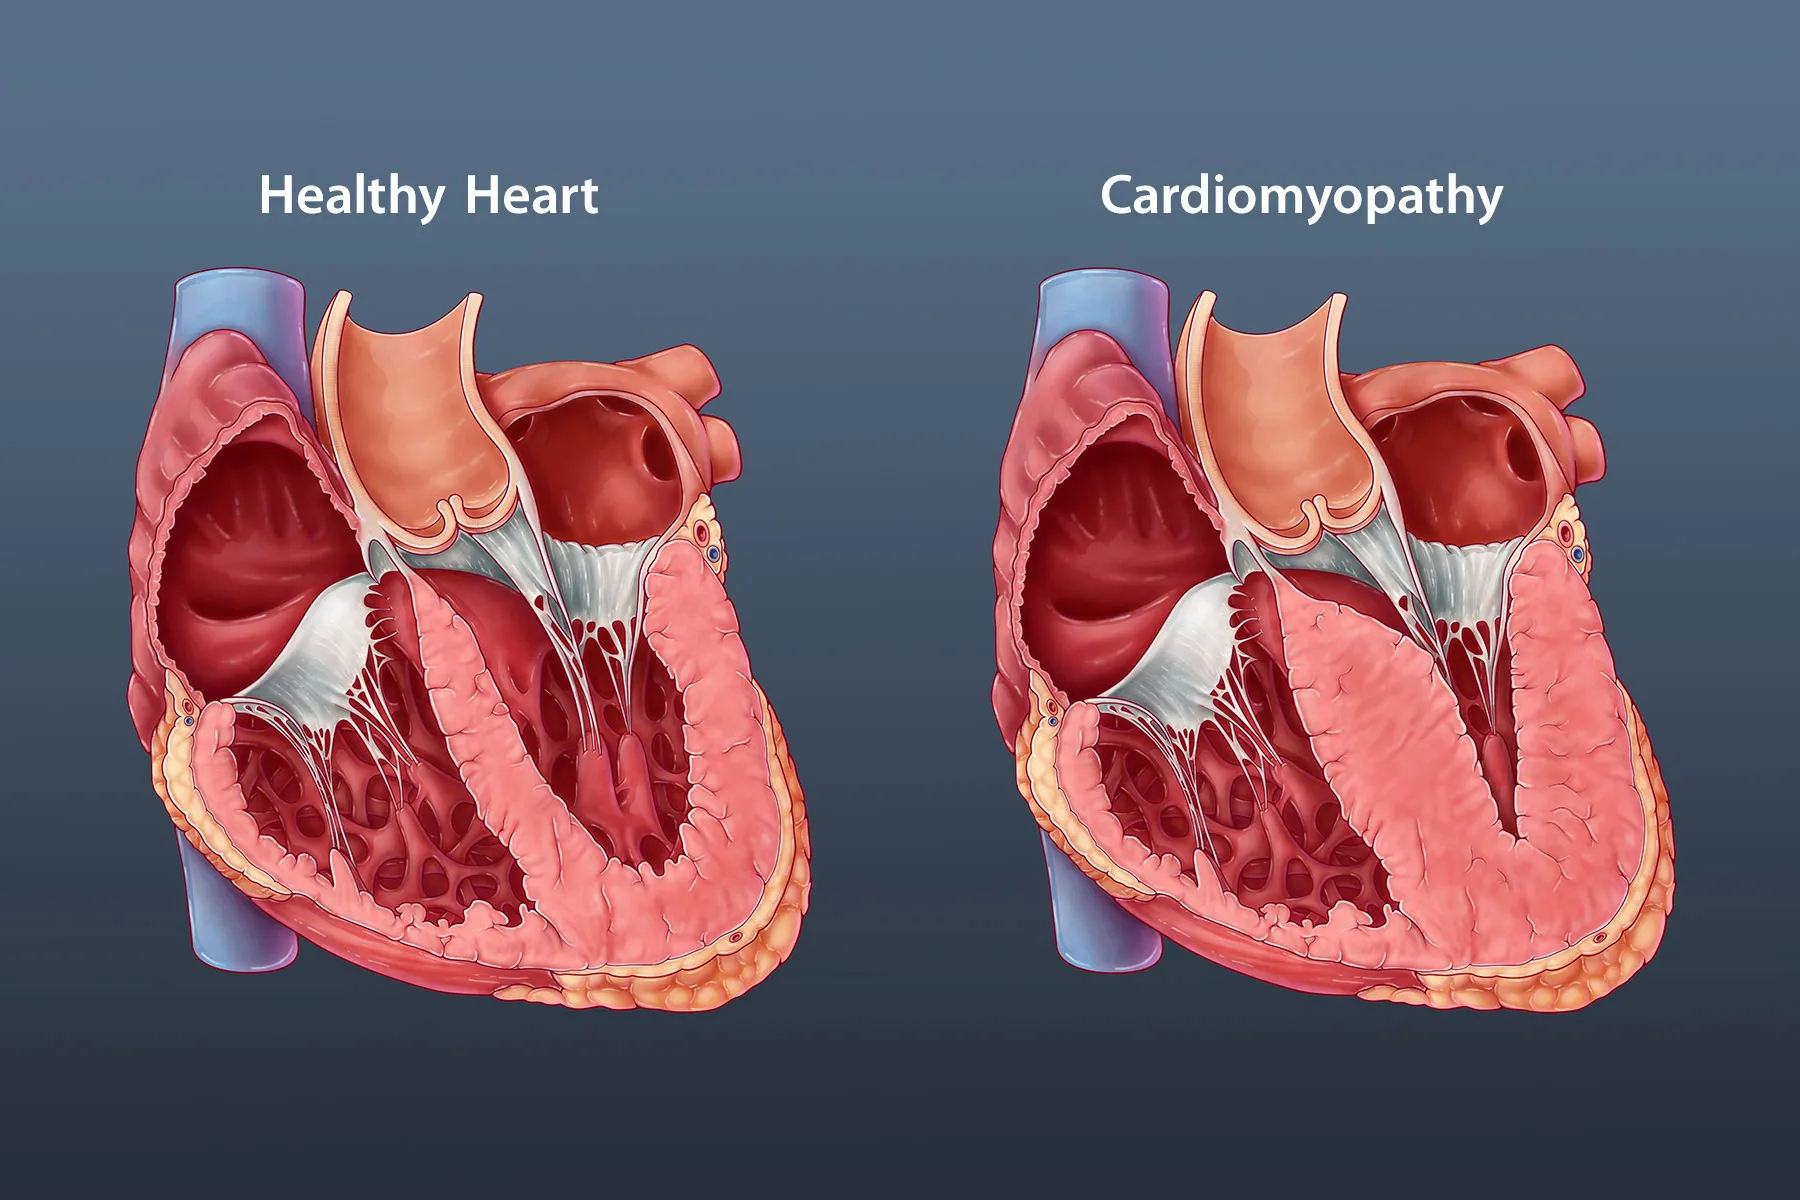

Qapaq xəstəlikləri Ürəkdə dörd ədəd qapaq mövcuddur – ürəyin sol tərəfində aort və mitral qapaq, sağ tərəfində isə pulmonar və trikuspid qapaqlar. Ürək qapaqlarının işi ürəyin işləmə fazasından asılı olaraq qanın ancaq müəyyən istiqamətdə hərəkətini təmin etməkdir. Məsələn, sağlam mitral qapaq qanın sol qulaqcıqdan sol mədəciyə doğru sürətli hərəkətini təmin…